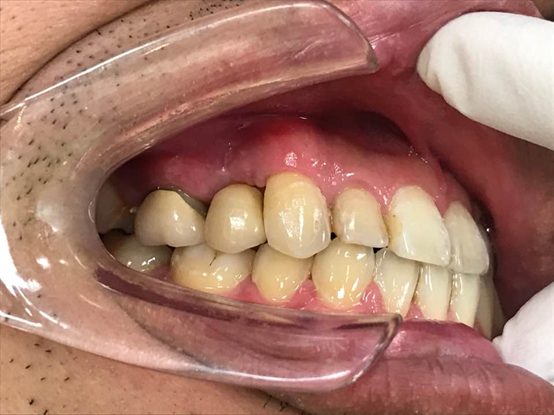

↑植牙療程結束!!

雖然療程時間有點久,但是可以感受的到郭醫師的用心!植牙過程中,郭醫師很仔細地幫我評估狀況,不會草率地看診,為了能有最好的植牙成效,每個階段都很謹慎、小心。不論是醫德還是醫術,郭醫師都是無可挑剔的好醫師!謝謝郭醫師細心的看診和護士們用心的照顧,澈底解決我的牙齒問題!如果你也有植牙需求,郭德樑醫師會是你最好的選擇!